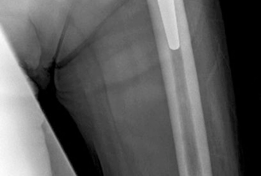

For anyone wondering about Acetabular Revision: Solving Challenges Post Two-Stage Arthroplasty, A **title acetabular revision** is a complex procedure addressing issues like septic loosening, dislocation, and significant osteolysis in total hip arthroplasty. For a 71-year-old male with a dislocated left THA due to infection and periacetabular bone loss, treatment involved a two-stage exchange followed by revision with a press-fit hemispherical cup and screw fixation.

Standard anteroposterior pelvis and cross-table lateral radiographs are mandatory. Judet views (iliac and obturator obliques) are critical for assessing the integrity of the anterior and posterior columns. However, plain radiography often underestimates the extent of osteolysis and bone loss.